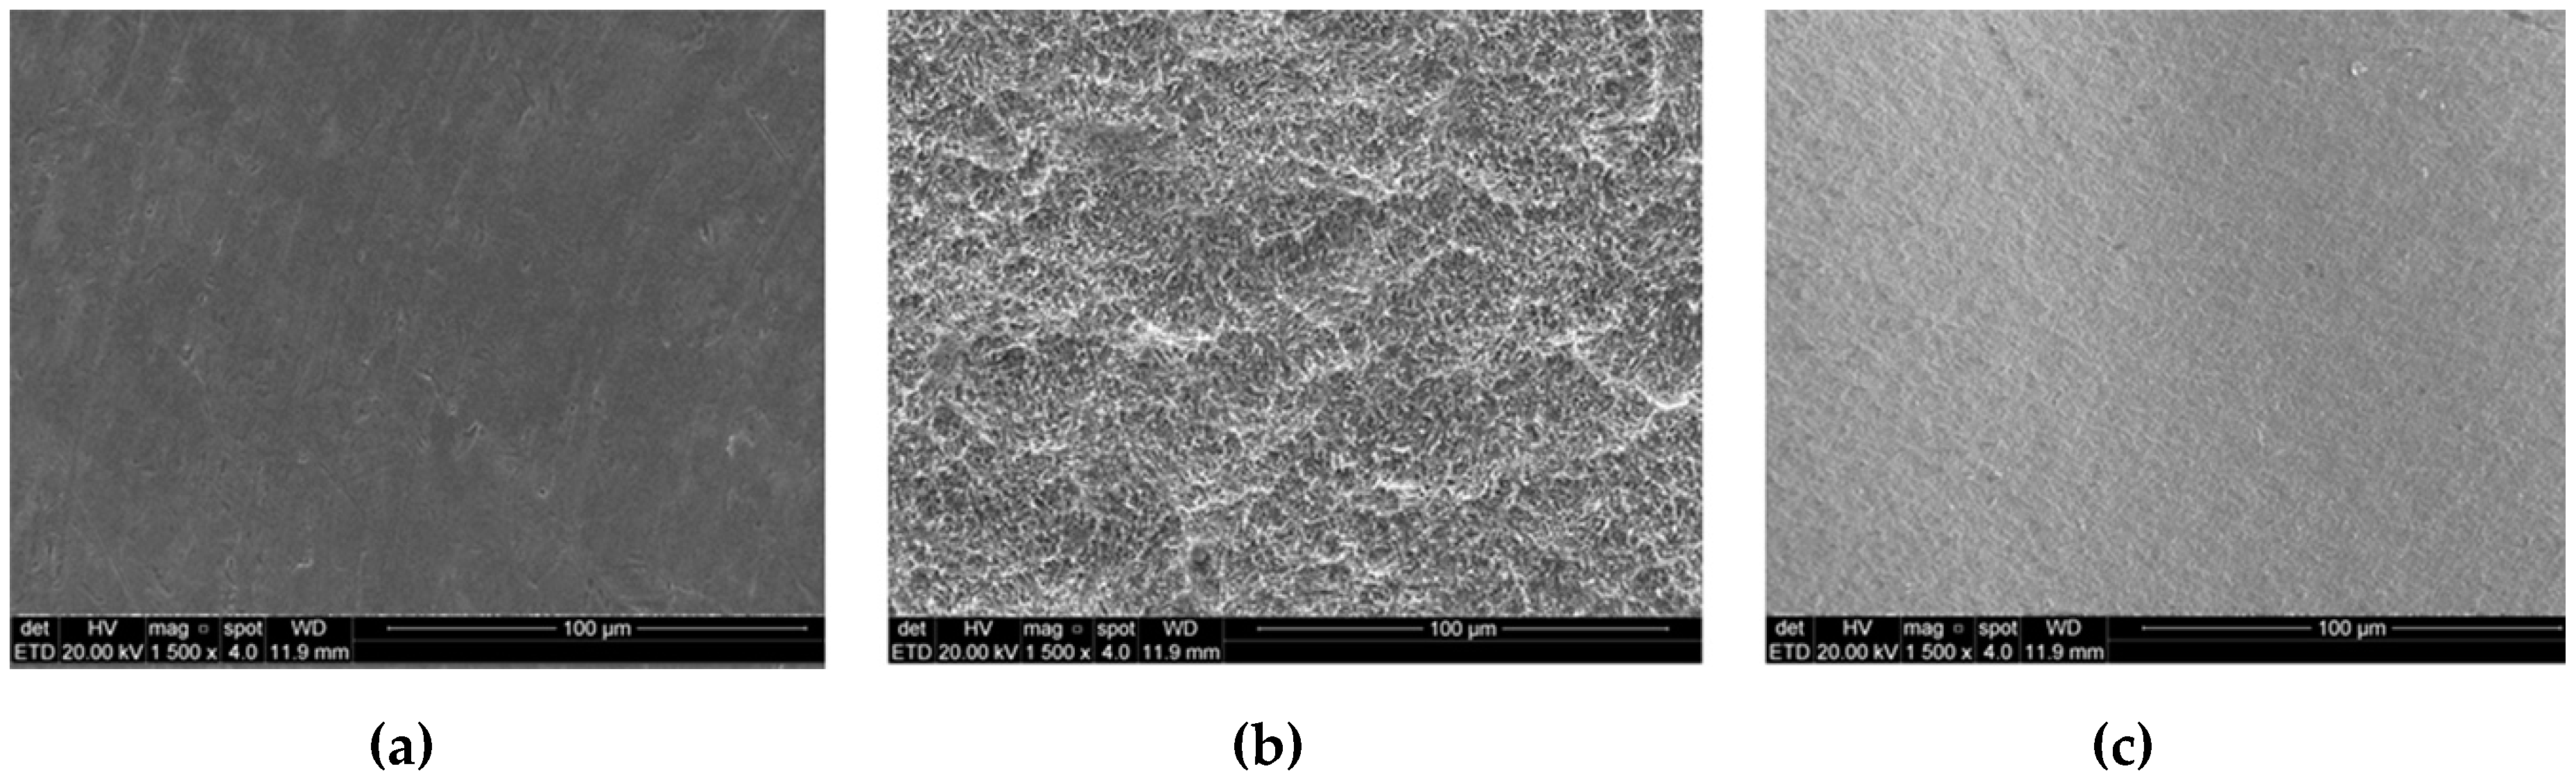

3.1. Surface Characterization Analysis